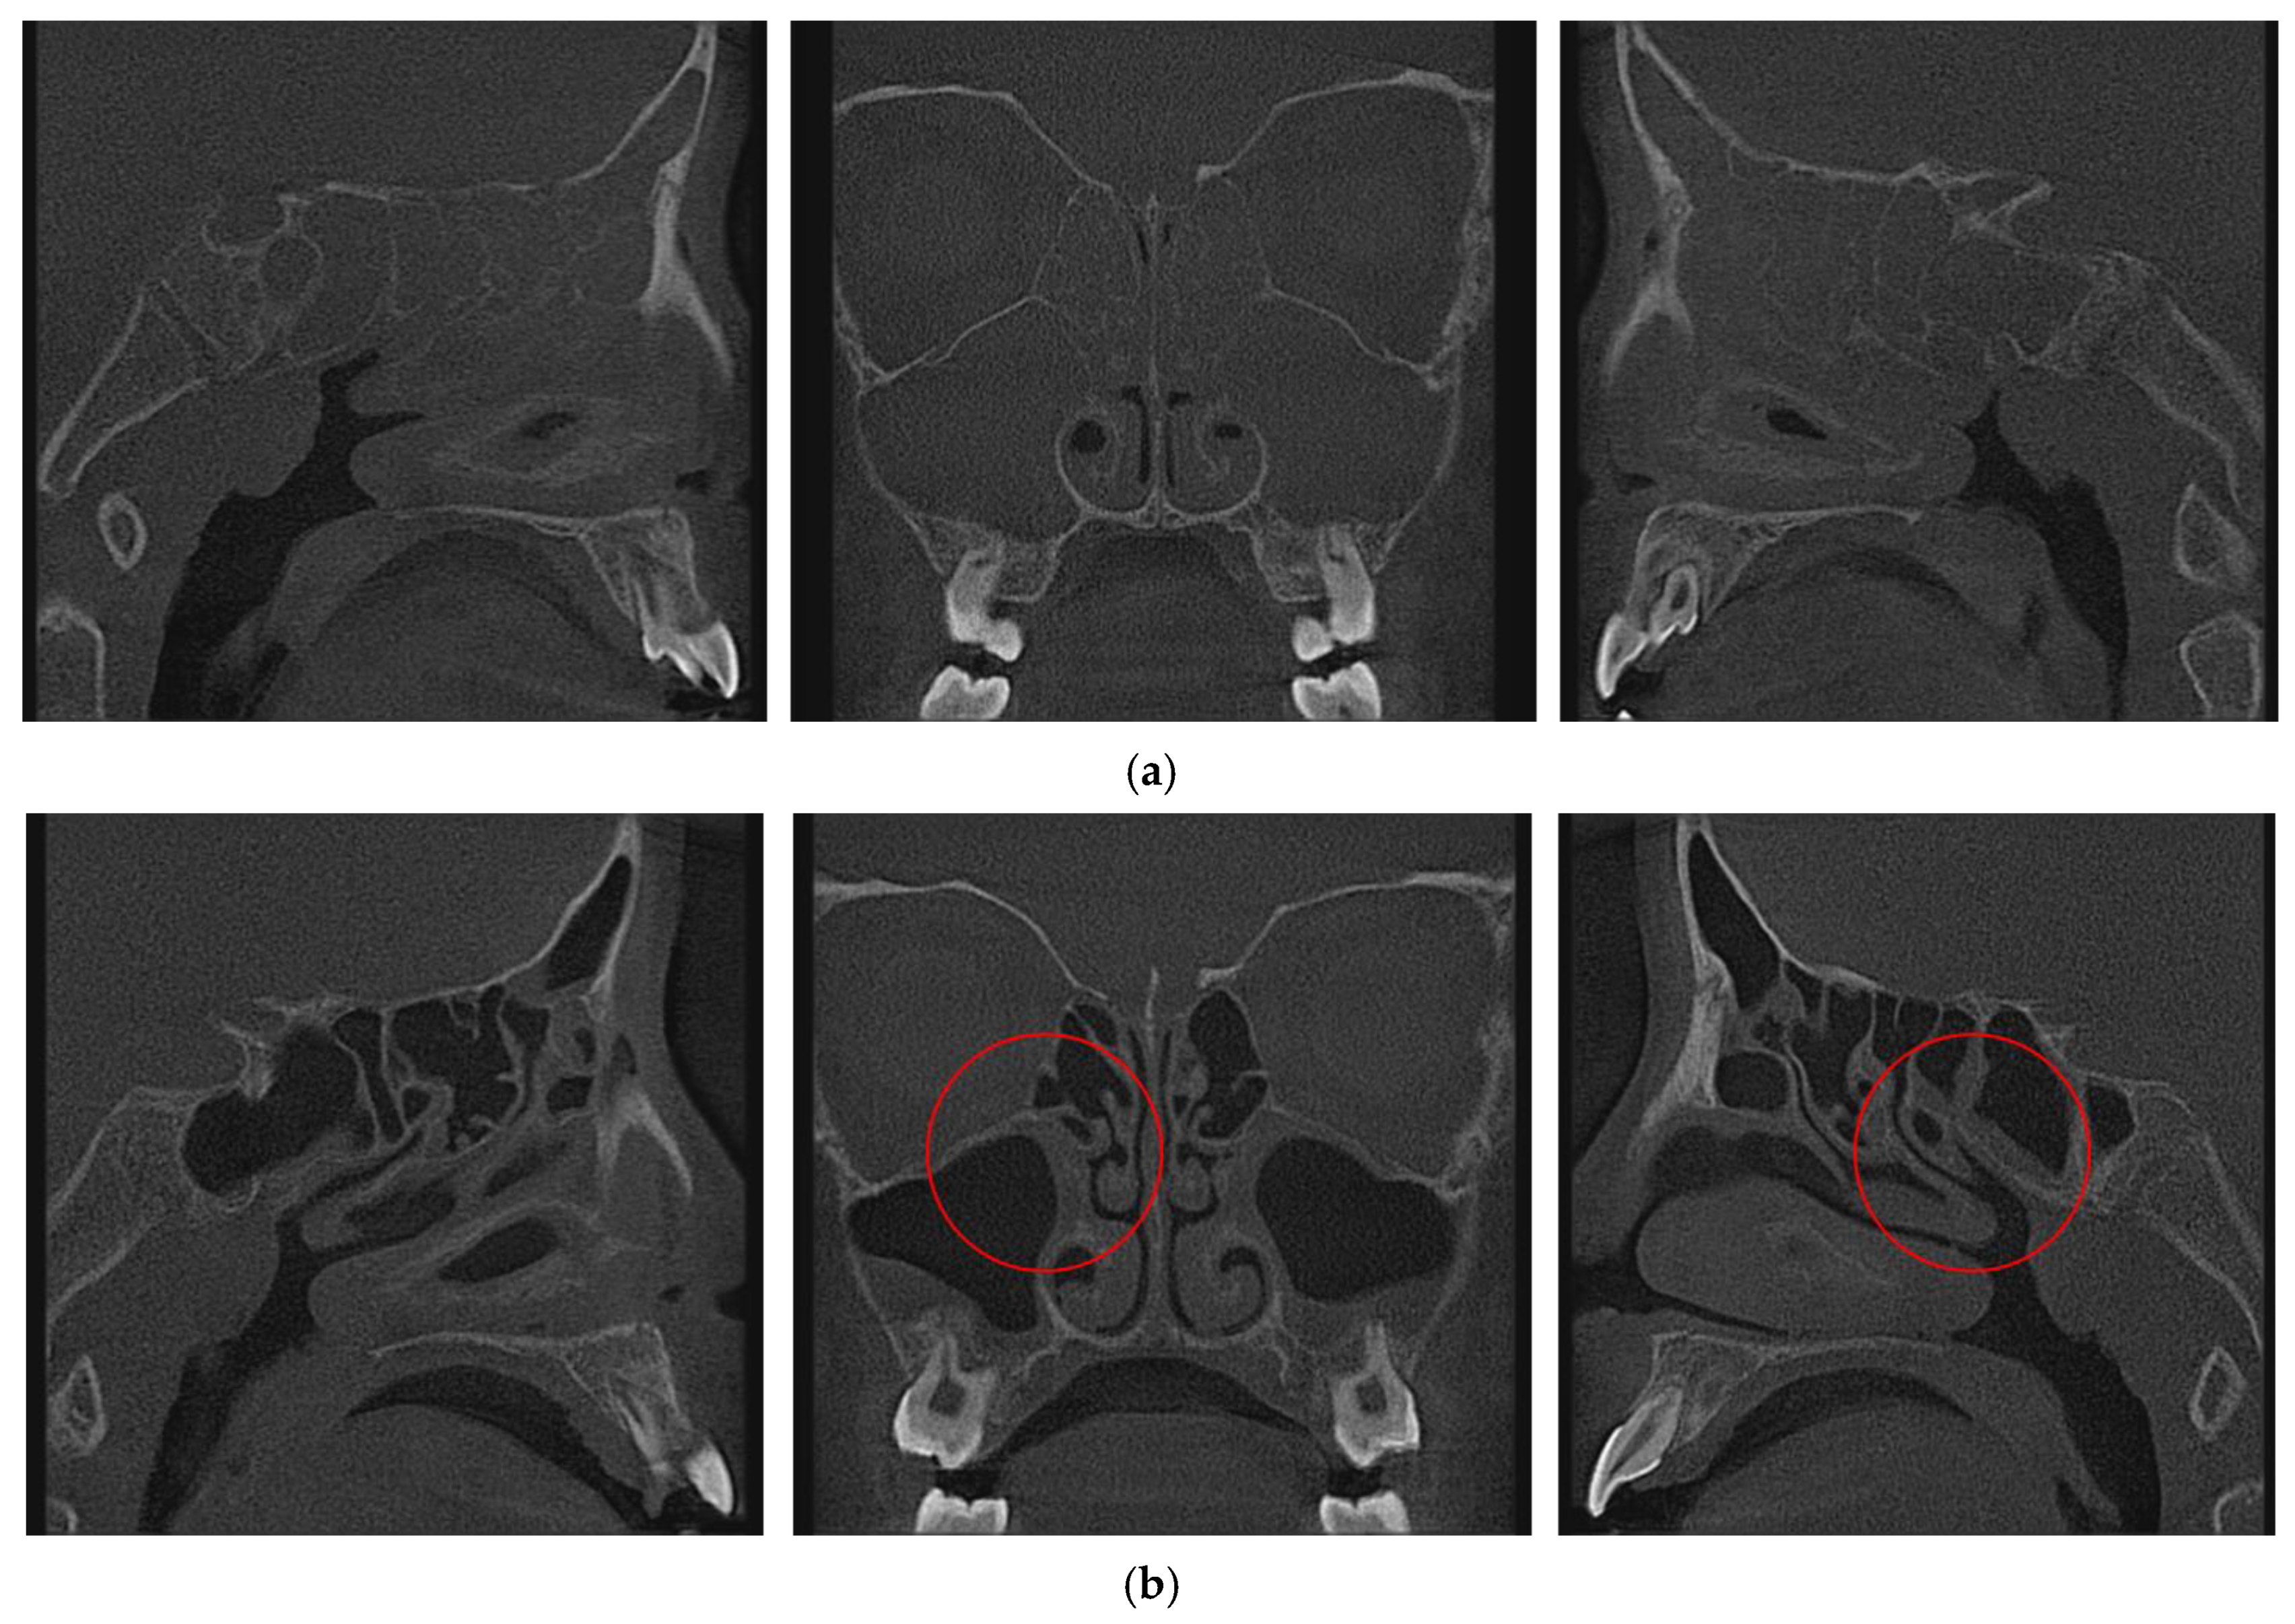

The Clear Sinus Group consisted of 26 patients (14 males, 12 females). The mean age at the first observation was approximately 6.6 years (6.8 ± 1.6 years for males, 6.4 ± 1.4 years for females), with an age range from 4 years 4 months to 11 years 0 months. Inclusion criteria for this group stipulated that patients presented with conditions deemed suitable for RAMPA therapy (such as unilateral or bilateral posterior crossbite or other orthodontic/craniofacial reasons) and, crucially, exhibited radiologically clear paranasal sinuses on their baseline cone-beam computed tomography (CBCT) scans. “Clear” was defined as the absence of significant mucosal thickening, fluid retention, or polypoid changes that could appreciably compromise baseline airway volume due to sinus pathology, opening the sinus ostium (Figure 1b).

The Opacified Sinus Group comprised 20 patients (7 males, 13 females). The mean age at the first observation was approximately 6.8 years (7.5 ± 3.3 years for males, 6.3 ± 1.9 years for females), with an age range from 4 years 1 month to 13 years 5 months. Inclusion criteria required patients to have conditions necessitating RAMPA therapy and to exhibit significant opacification in one or more paranasal sinuses on baseline CBCT scans. “Opacification” was defined as the presence of radiopaque material within the sinus cavity, indicative of conditions such as sinusitis, significant mucosal inflammation, or mucus retention, which were presumed to contribute to a reduced baseline airway volume. Radiological classification of paranasal sinus status (clear versus opacified) was performed using predefined CBCT-based criteria by the examiner. All assessments were conducted by a single experienced examiner, and formal inter-observer reliability testing was not performed. These patients were also noted to have been diagnosed with rhinosinusitis by an otolaryngologist, swelling of the mucosa by 1 mm or more, and blocking the sinus ostium (Figure 1a).

Figure 1. CBCT Images for paranasal sinuses: (a) Opacified Paranasal Sinuses (obstruction of sinus ostium, Mucosal thickening of 1 mm or more), (b) Clear Paranasal Sinuses (opening of sinus ostium).